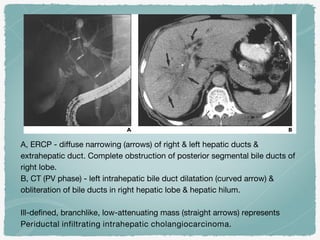

A, ERCP - diffuse narrowing (arrows) of right & left hepatic ducts &

extrahepatic duct. Complete obstruction of posterior segmental bile ducts of

right lobe.

B, CT (PV phase) - left intrahepatic bile duct dilatation (curved arrow) &

obliteration of bile ducts in right hepatic lobe & hepatic hilum.

Ill-defined, branchlike, low-attenuating mass (straight arrows) represents

Periductal infiltrating intrahepatic cholangiocarcinoma.